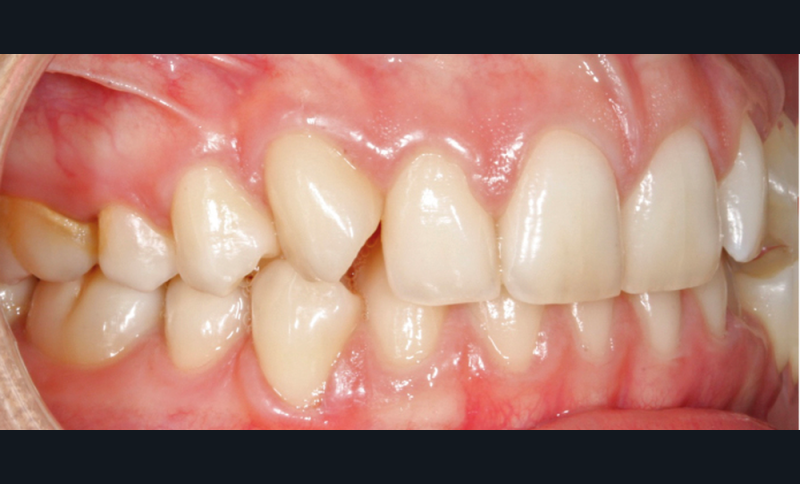

L’examen intra-arcade met en évidence une hygiène bucco-dentaire irréprochable, favorable à un traitement en technique linguale. Le phénotype parodontal est fin dans la région incisivo-canine mandibulaire. L’encombrement est estimé à 8 mm à la mandibule et à 4 mm au maxillaire (fig. 1). Les arcades ont des formes similaires, en U. Les rapports inter-arcades mettent en évidence une classe 1 d’Angle molaire, une classe 2 d’Angle canine et une supraclusion antérieure (recouvrement : 5 mm ; surplomb diminué). Les milieux inter-incisifs sont déviés entre eux avec une origine mixte (= 1,5 mm) (fig. 2).